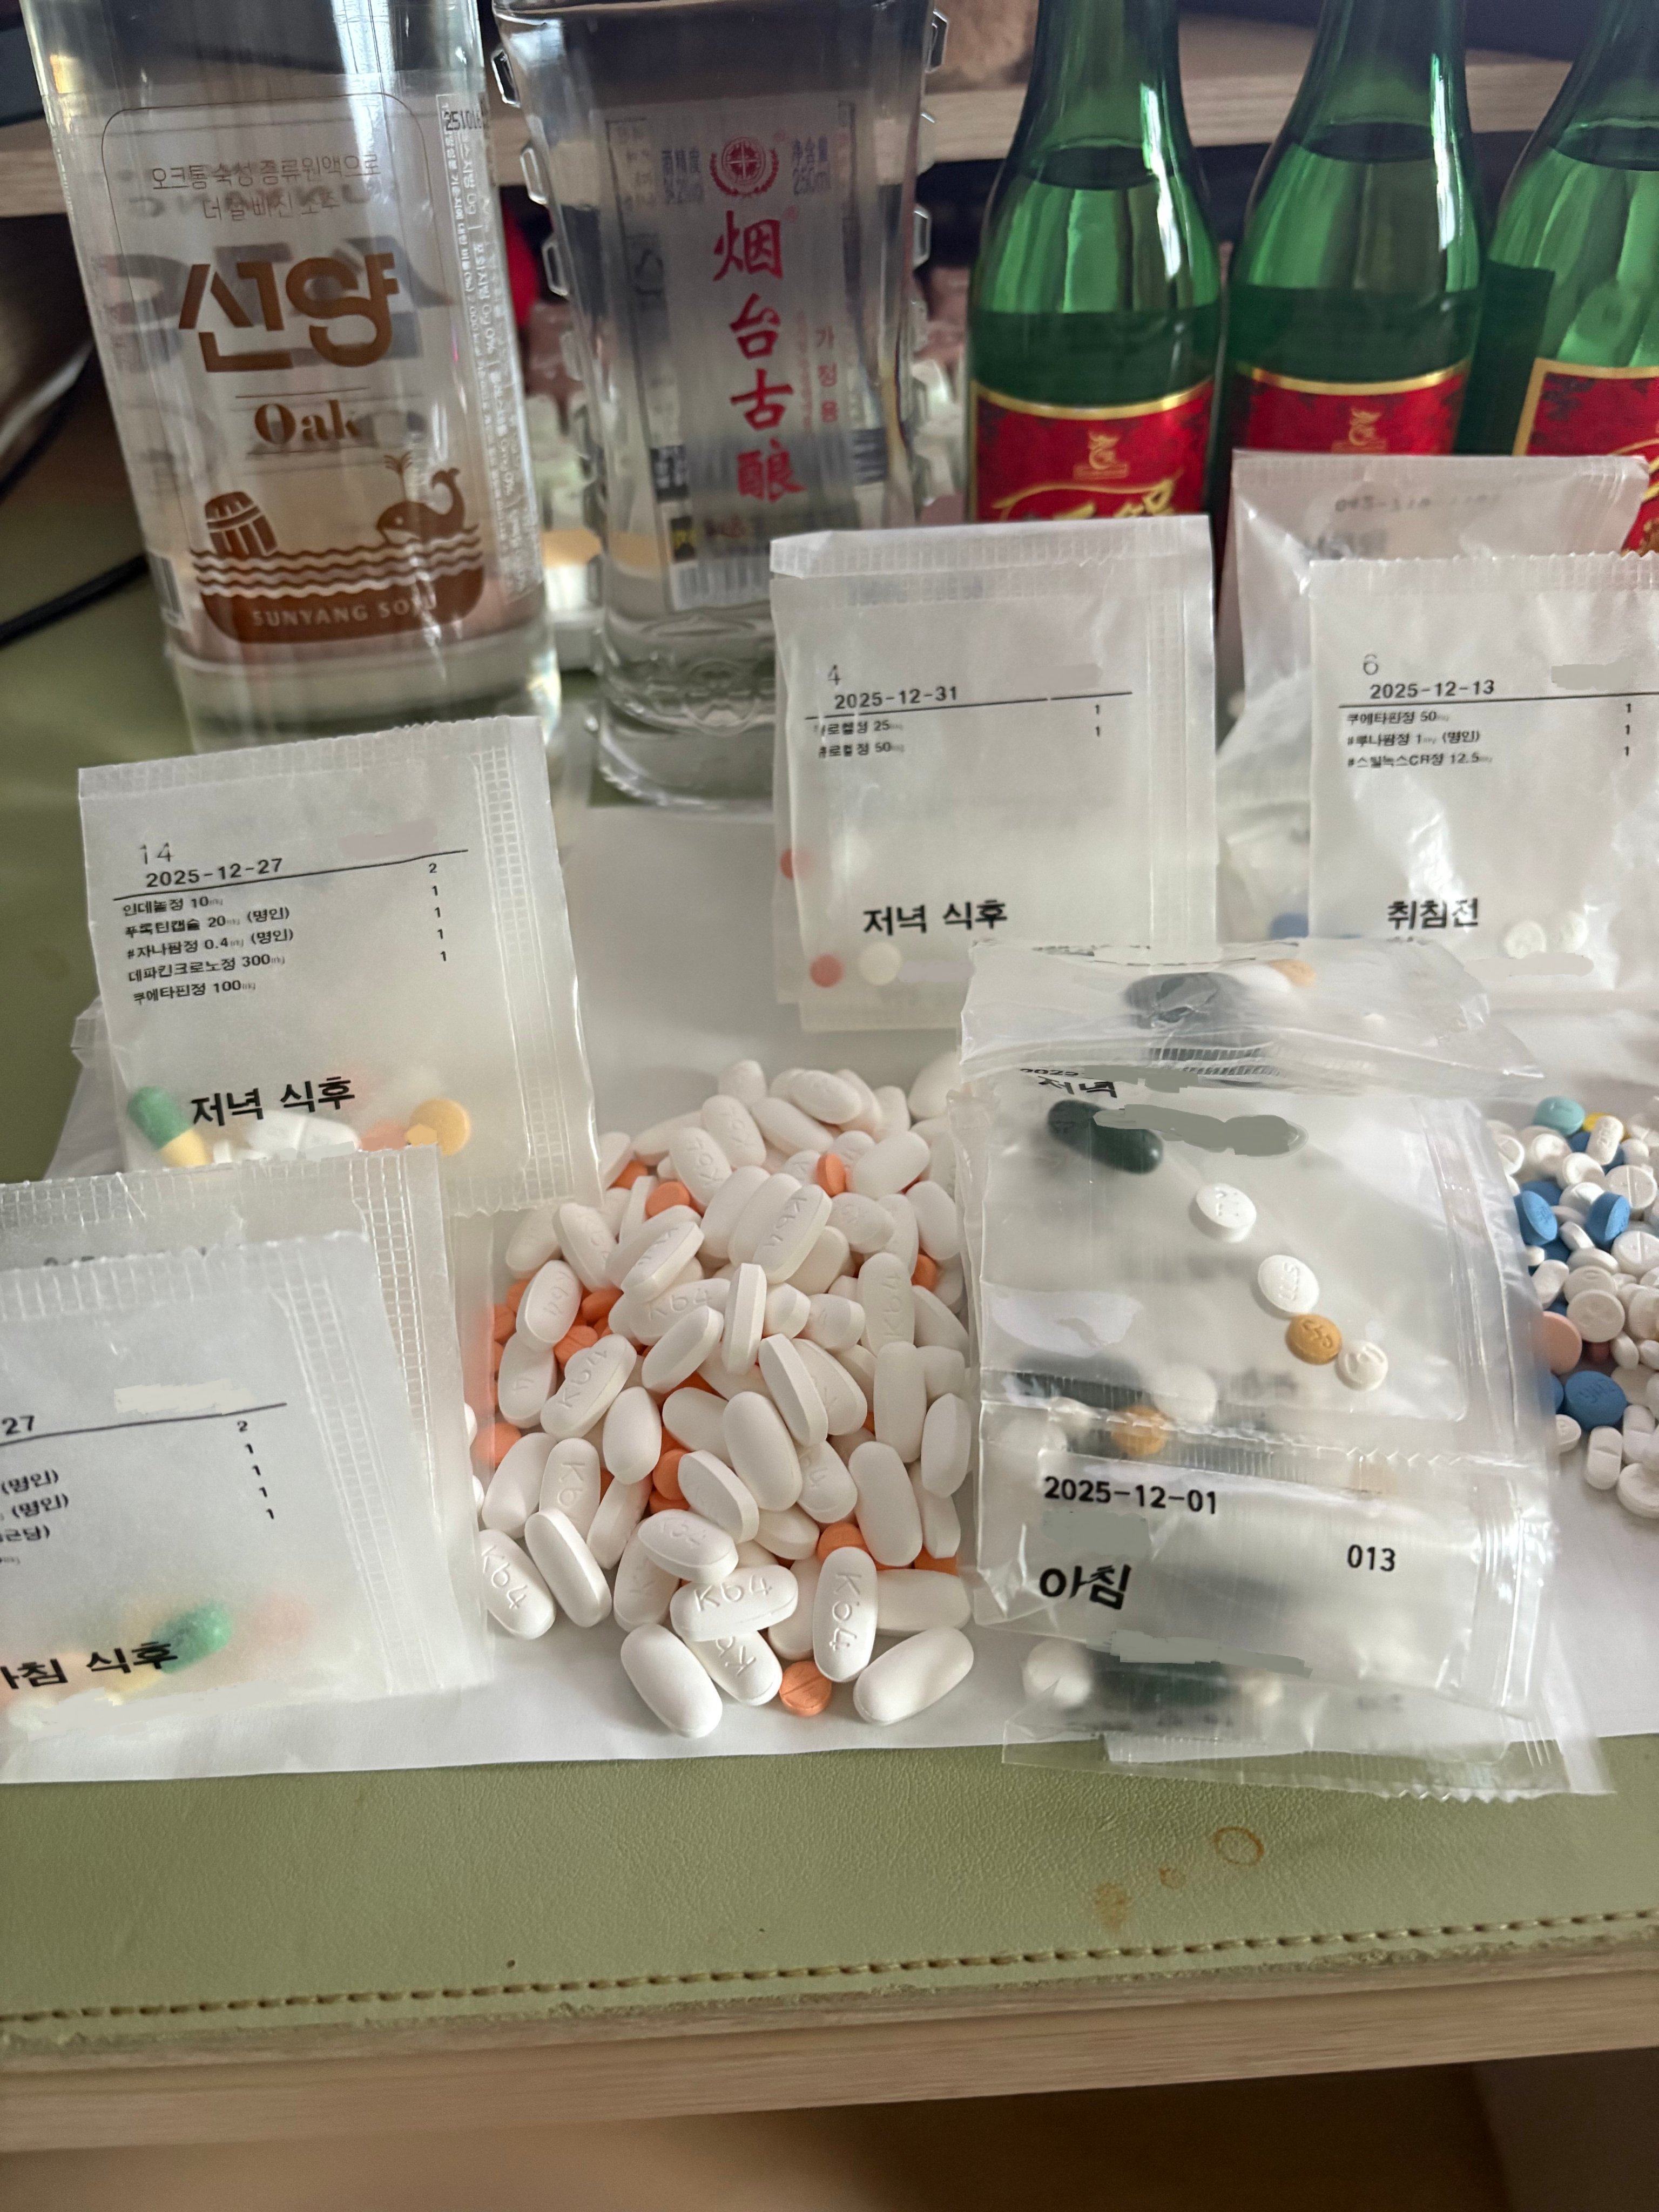

对于药物过量引起的中枢神经系统副作用,有一些不常见或常见的药物来控制症状。

罗通定:拮抗多巴胺

赛庚啶:血清素综合症

异丙嗪:在低剂量下没有抗精神病作用,和其他所有抗组胺药一样可以缓解过敏。止吐

喹硫平:不清楚是什么引起的症状就干脆谁都别玩了吧()似乎很万能的急救

评论区欢迎补充 https://t.co/7S4tGVDEM5